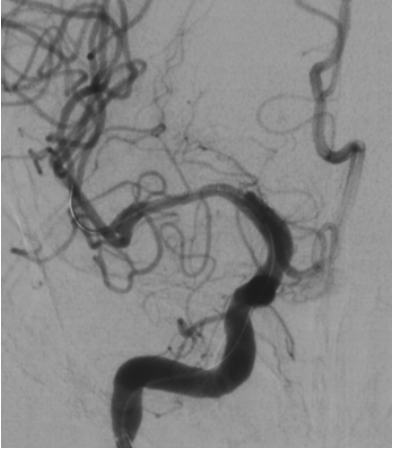

植入Neuroform EZ 4.5/20支架,残余狭窄约20%;术后患者恢复良好出院。继续抗血小板聚集及他汀类药物调脂治疗

DSA复查(2019-10-31)提示严重支架内狭窄,豆纹动脉及早期颞支动脉依然保持通畅